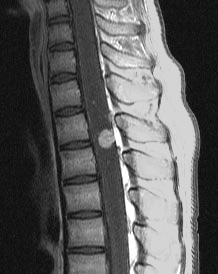

フォン・ヒッペル・リンドウ病の患者さんの脊髄(胸髄)にできた血管芽腫です。上下の脊髄が腫れたり,脊髄の中に空洞(腫瘍のう胞あるいは脊髄空洞症といいます)ができます。 手術治療は症状が出るまで,あるいは症状がかなり強くなってからしかしません。なぜなら,たくさんできる(多発)することが多くて,複数回の手術になってしまうこともあるからです。手術をするたびに,四肢のしびれや麻痺などの後遺症がのこる可能性もあるので,この手術は,脊髄腫瘍の手術経験が相当にたくさんある脳外科医にしかできません。